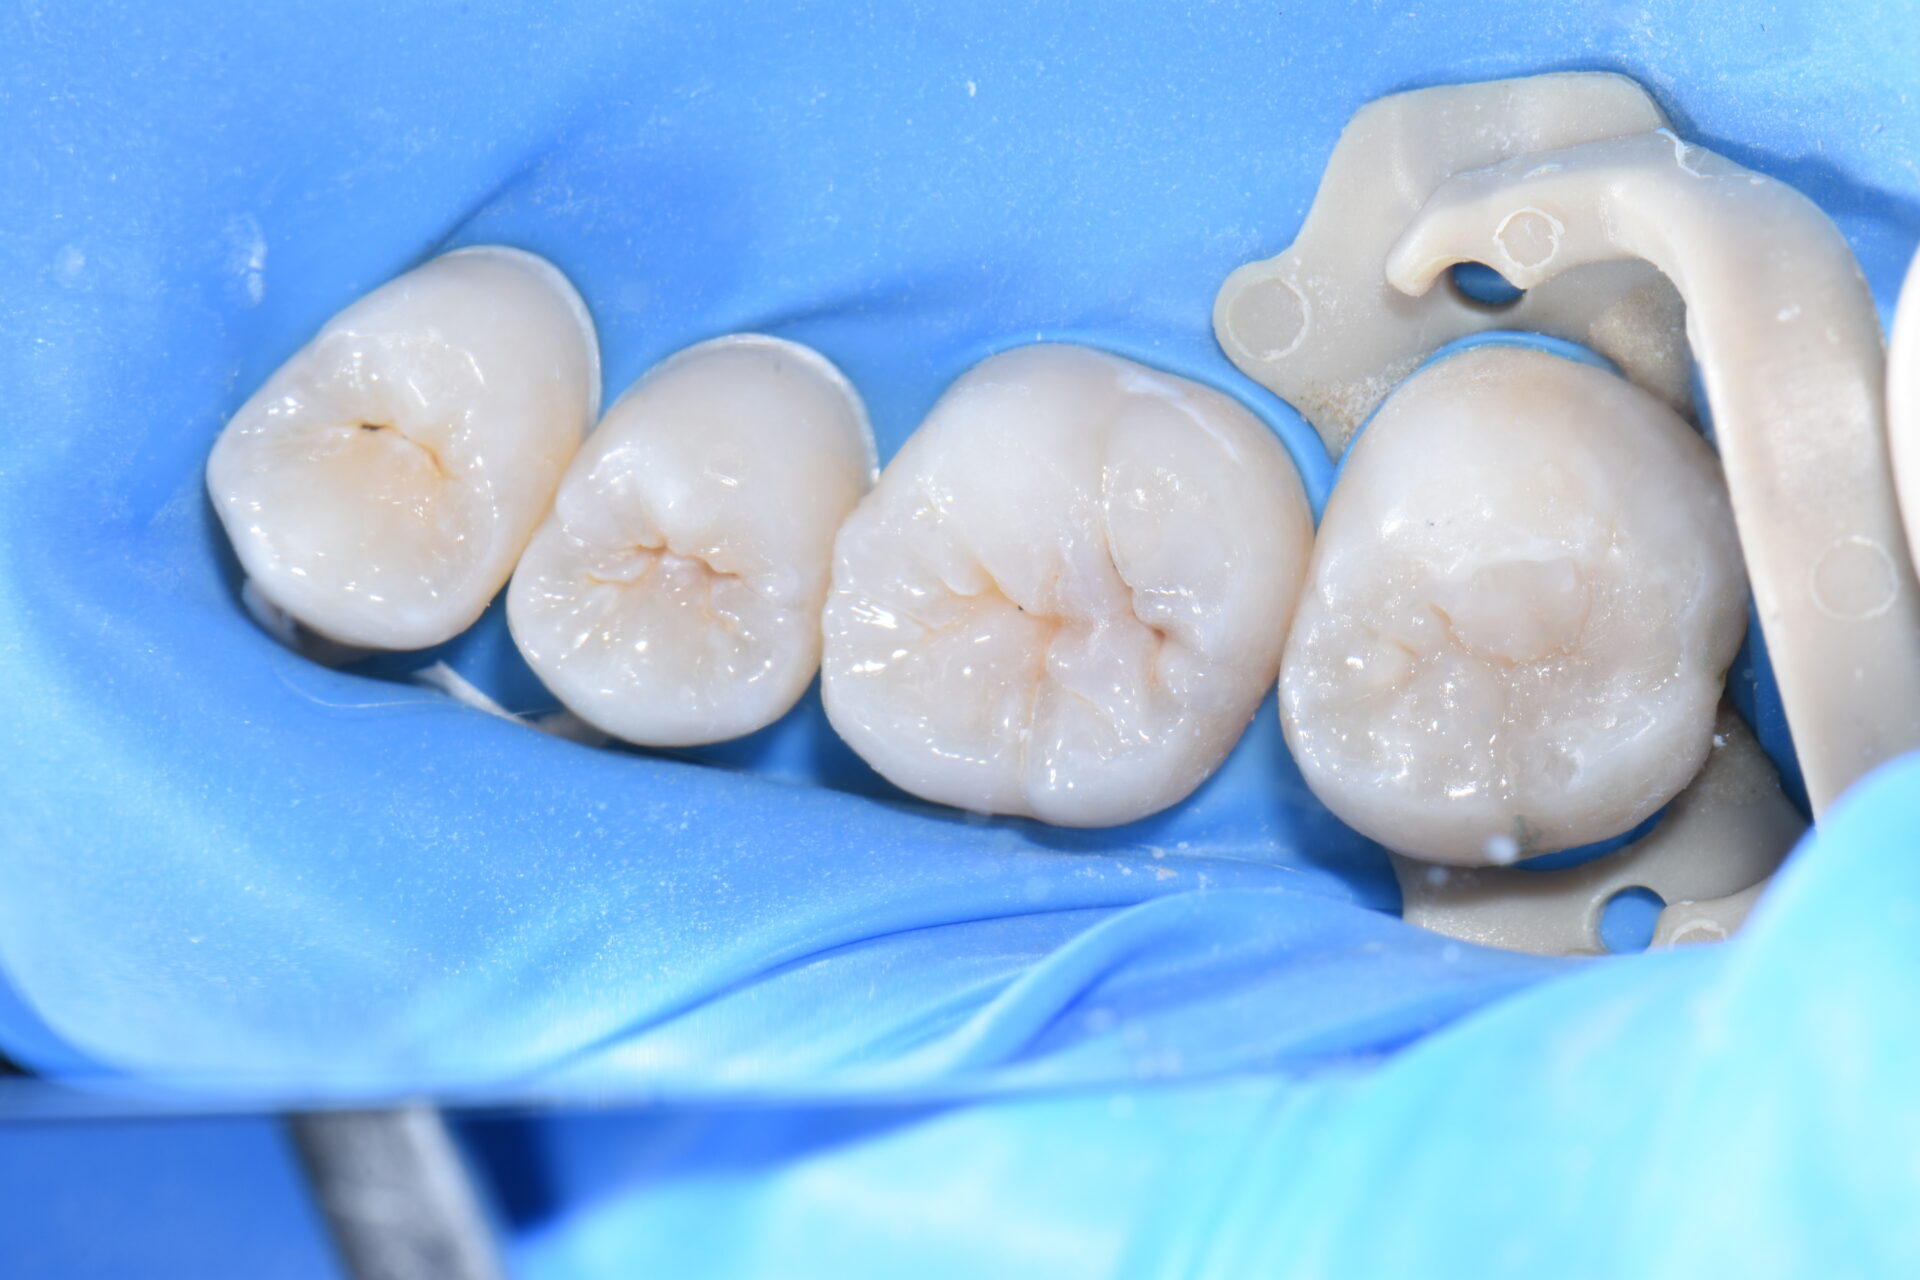

術前 歯科健診と歯のクリーニングで来院。第二大臼歯に虫歯が見つかりました。

無自覚無症状で大変小さな虫歯に見えますが実は大きな虫歯です。